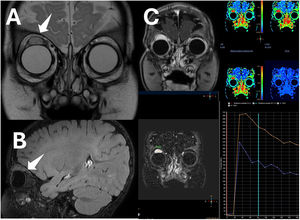

Magnetic resonance imaging. (A) Coronal view and (B) sagittal view showing a homogeneous lesion, hyperintense on T2-weighted imaging, in the distal portion of the superior rectus muscle of the right eye, near the insertion on the globe, measuring 16 × 14 × 16 mm (anteroposterior × transverse × craniocaudal diameters), with a hypointense border corresponding to a pseudocapsule, showing facilitated diffusion, without calcification or bleeding within the lesion. (C) Dynamic contrast-enhanced MRI, fat-suppressed T1-weighted images showing a type 3 kinetic curve with a rapid uptake followed by a progressive reduction on the late phase (washout). Post-contrast imaging of the right superior rectus muscle showing homogeneous enhancement.

An infant aged 4 months was referred for assessment of a purplish mass in the posterior surface of the right upper eyelid (Fig. 1), with no other abnormalities in the ophthalmological examination. Magnetic resonance imaging revealed a well-defined intramuscular mass in the superior rectus muscle of the right eye with characteristics suggestive—but not pathognomonic—of hemangioma (Fig. 2). The patient underwent an incisional biopsy at age 9 months. The histological analysis revealed proliferation of small-caliber vessels without atypia. Immunohistochemical staining was positive for GLUT-1, CD34 and WT-1, confirming the diagnosis of infantile hemangioma (Fig. 3). The patient started treatment with oral propranolol (Hemangiol), which was well tolerated and achieved a favorable response.1 Follow-up MRI scans showed progressive involution and fibrotic changes.